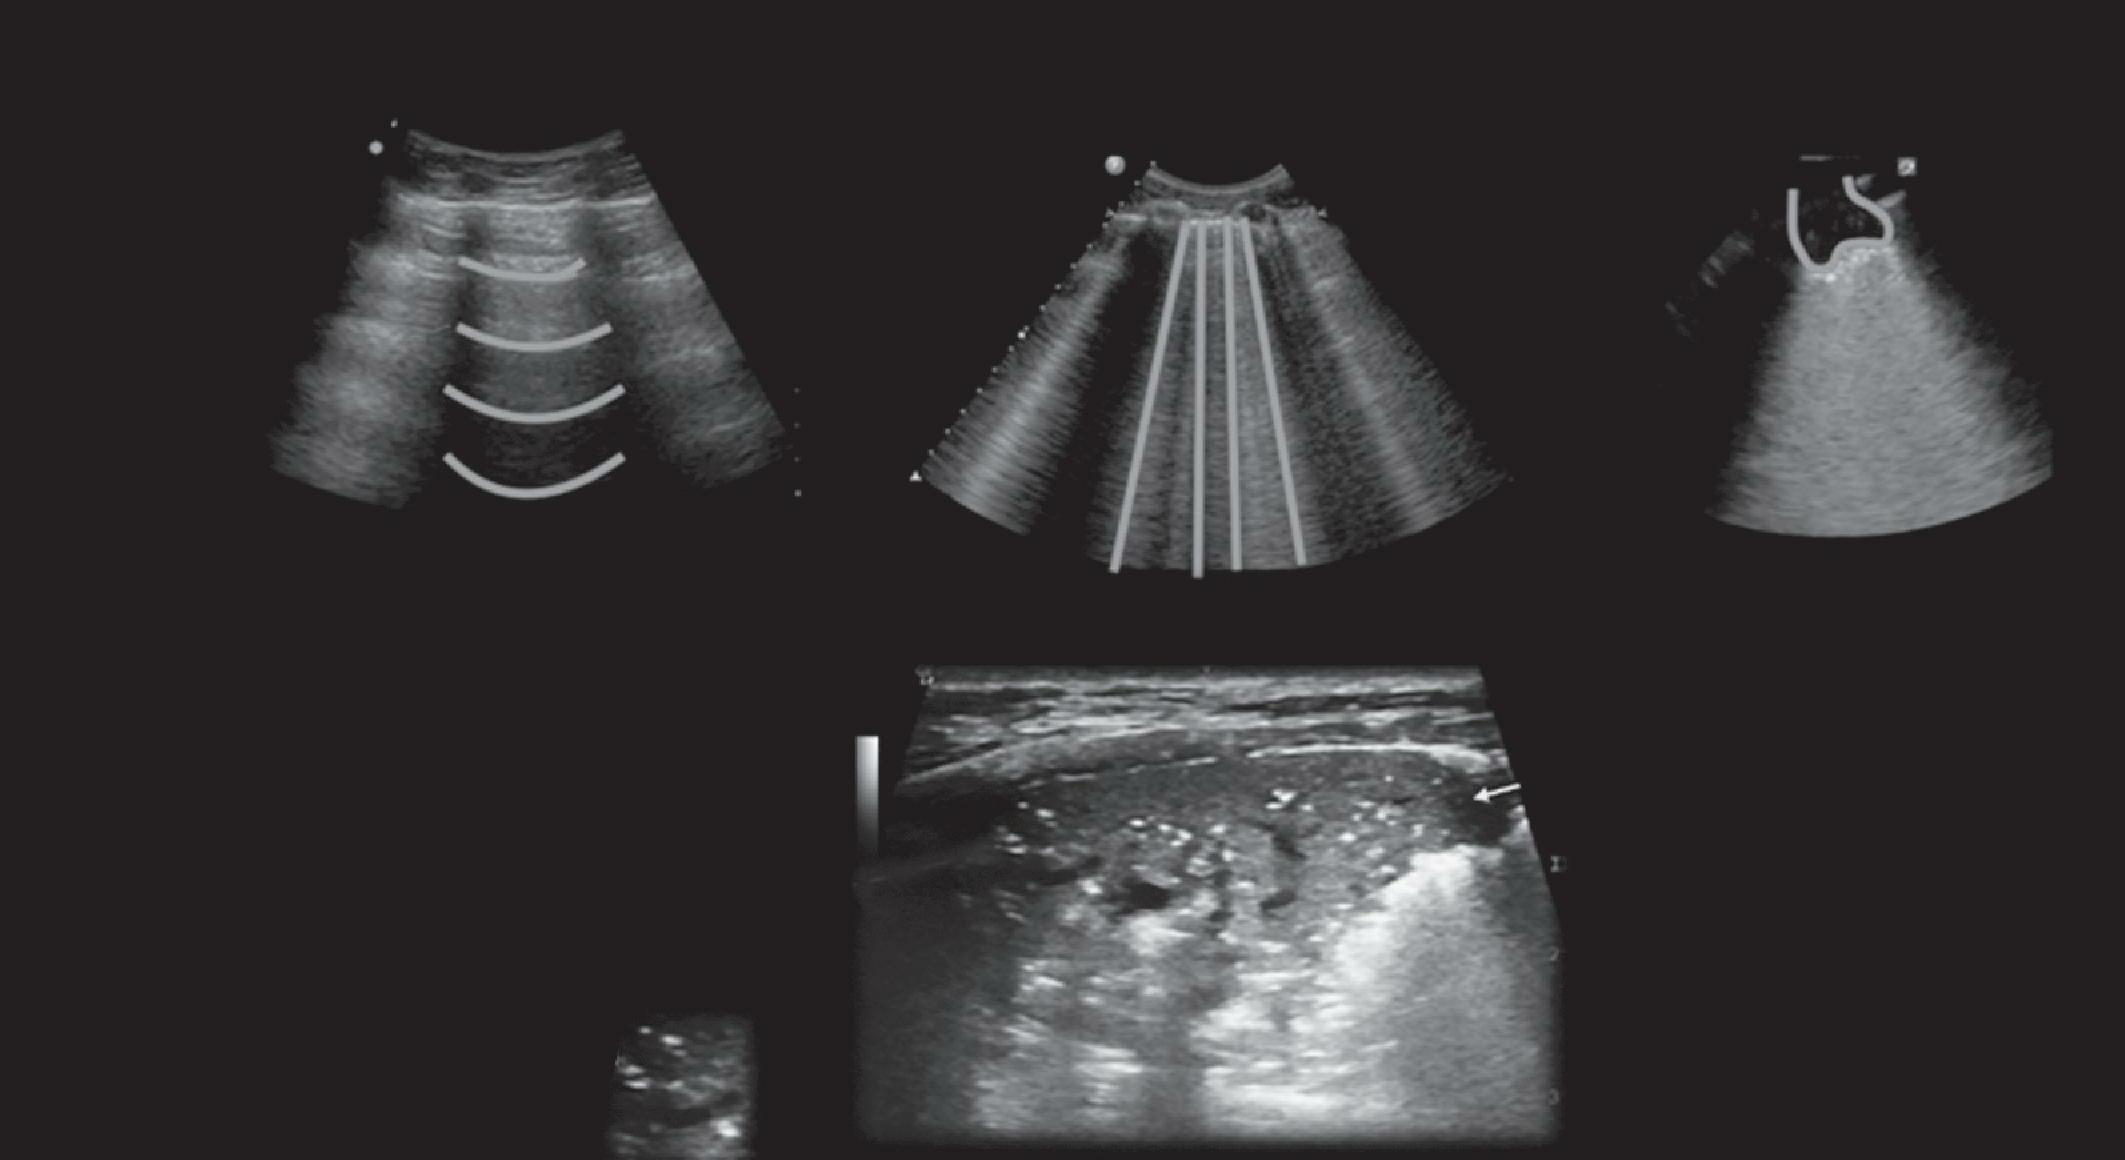

Ultrassom Point of Care e sua Aplicabilidade

Figura 10.2 (A e B) Radiografia de tórax (A) e eletrocardiograma (B) de paciente com tamponamento no pósoperatório imediato